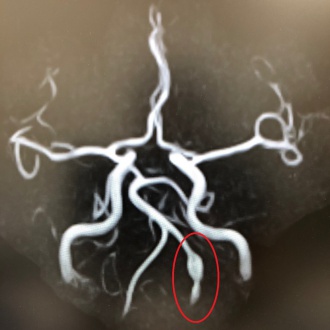

一つは一般的な「くも膜下出血」で、脳血管の弱い部分が膨らんだ『脳動脈瘤』が破裂することで発症します。もう一つが『解離性脳動脈瘤』で、3層構造になっている血管の壁の1層目、あるいは2層目がメリメリと裂けて、血管壁の中側に血液が入り込んで膨らみます。これが破裂したのが、解離性脳動脈瘤破裂によるくも膜下出血です。

解離性脳動脈瘤は首の後ろ側にある2本の椎骨動脈にできることが多く、そのきっかけとなるのが、首をひねる行為です。